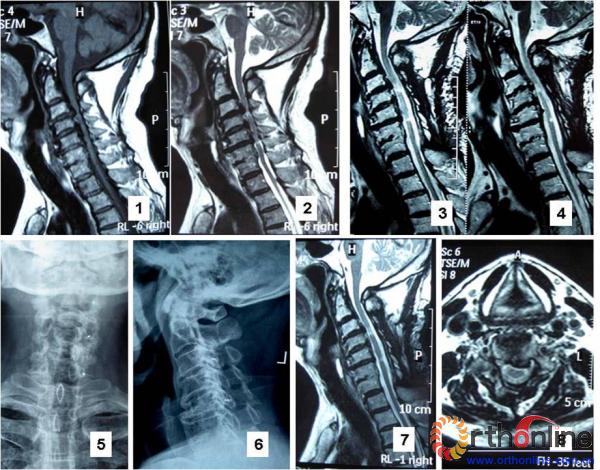

图2 苏XX,64岁,多节段脊髓型颈椎病,伴发育性颈椎管狭窄。1,2:术前颈椎MRI,多节段脊髓严重受压;3,4:术后0.5年颈椎MRI,脊髓前后方压迫解除;5,6:术后1.2年颈椎正侧位X线片,可见3个锚钉影像位置良好,椎管扩大,无再关门;7,8:术后1.2年MRI显示,C3-7脊髓前后方无压迫,病人疗效为优